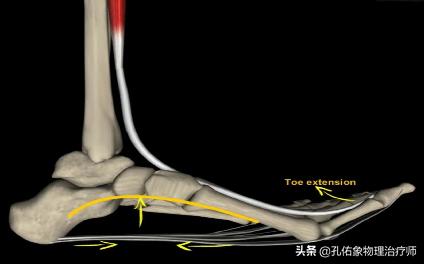

在我们的脚底有一层致密的结缔组织——跖筋膜,如下图所示,它既不是韧带、也不是肌腱,但是其作用却非常的重要,它可以维持我们的足弓形态结构和足底的张力。

我们每天都要不停地行走、跑、跳,会反复地牵拉足底筋膜,特别是足底筋膜与跟骨连接的位置较为明显,久而久之, 会使足底筋膜发生退变及劳损 。

所以,您会经常感觉在 跟骨大结节与跖筋膜结合处疼痛 ,特别是按压时更痛苦;最典型的症状是在晨起下地那一瞬间。这是我们日常生活中最多见的一类足底痛,不要轻易被诊断为骨刺痛。

您需要明白,骨刺与您的疼痛症状没有相关性,哪怕是拍了脚踝的X线片,上面长有骨刺,都不要误认为疼痛就是骨刺引起的; 因为骨刺的形成是足底跖筋膜与跟骨连接部位反复地出现撕裂瘢痕,最终钙化所致;其根源还是足底的跖筋膜。